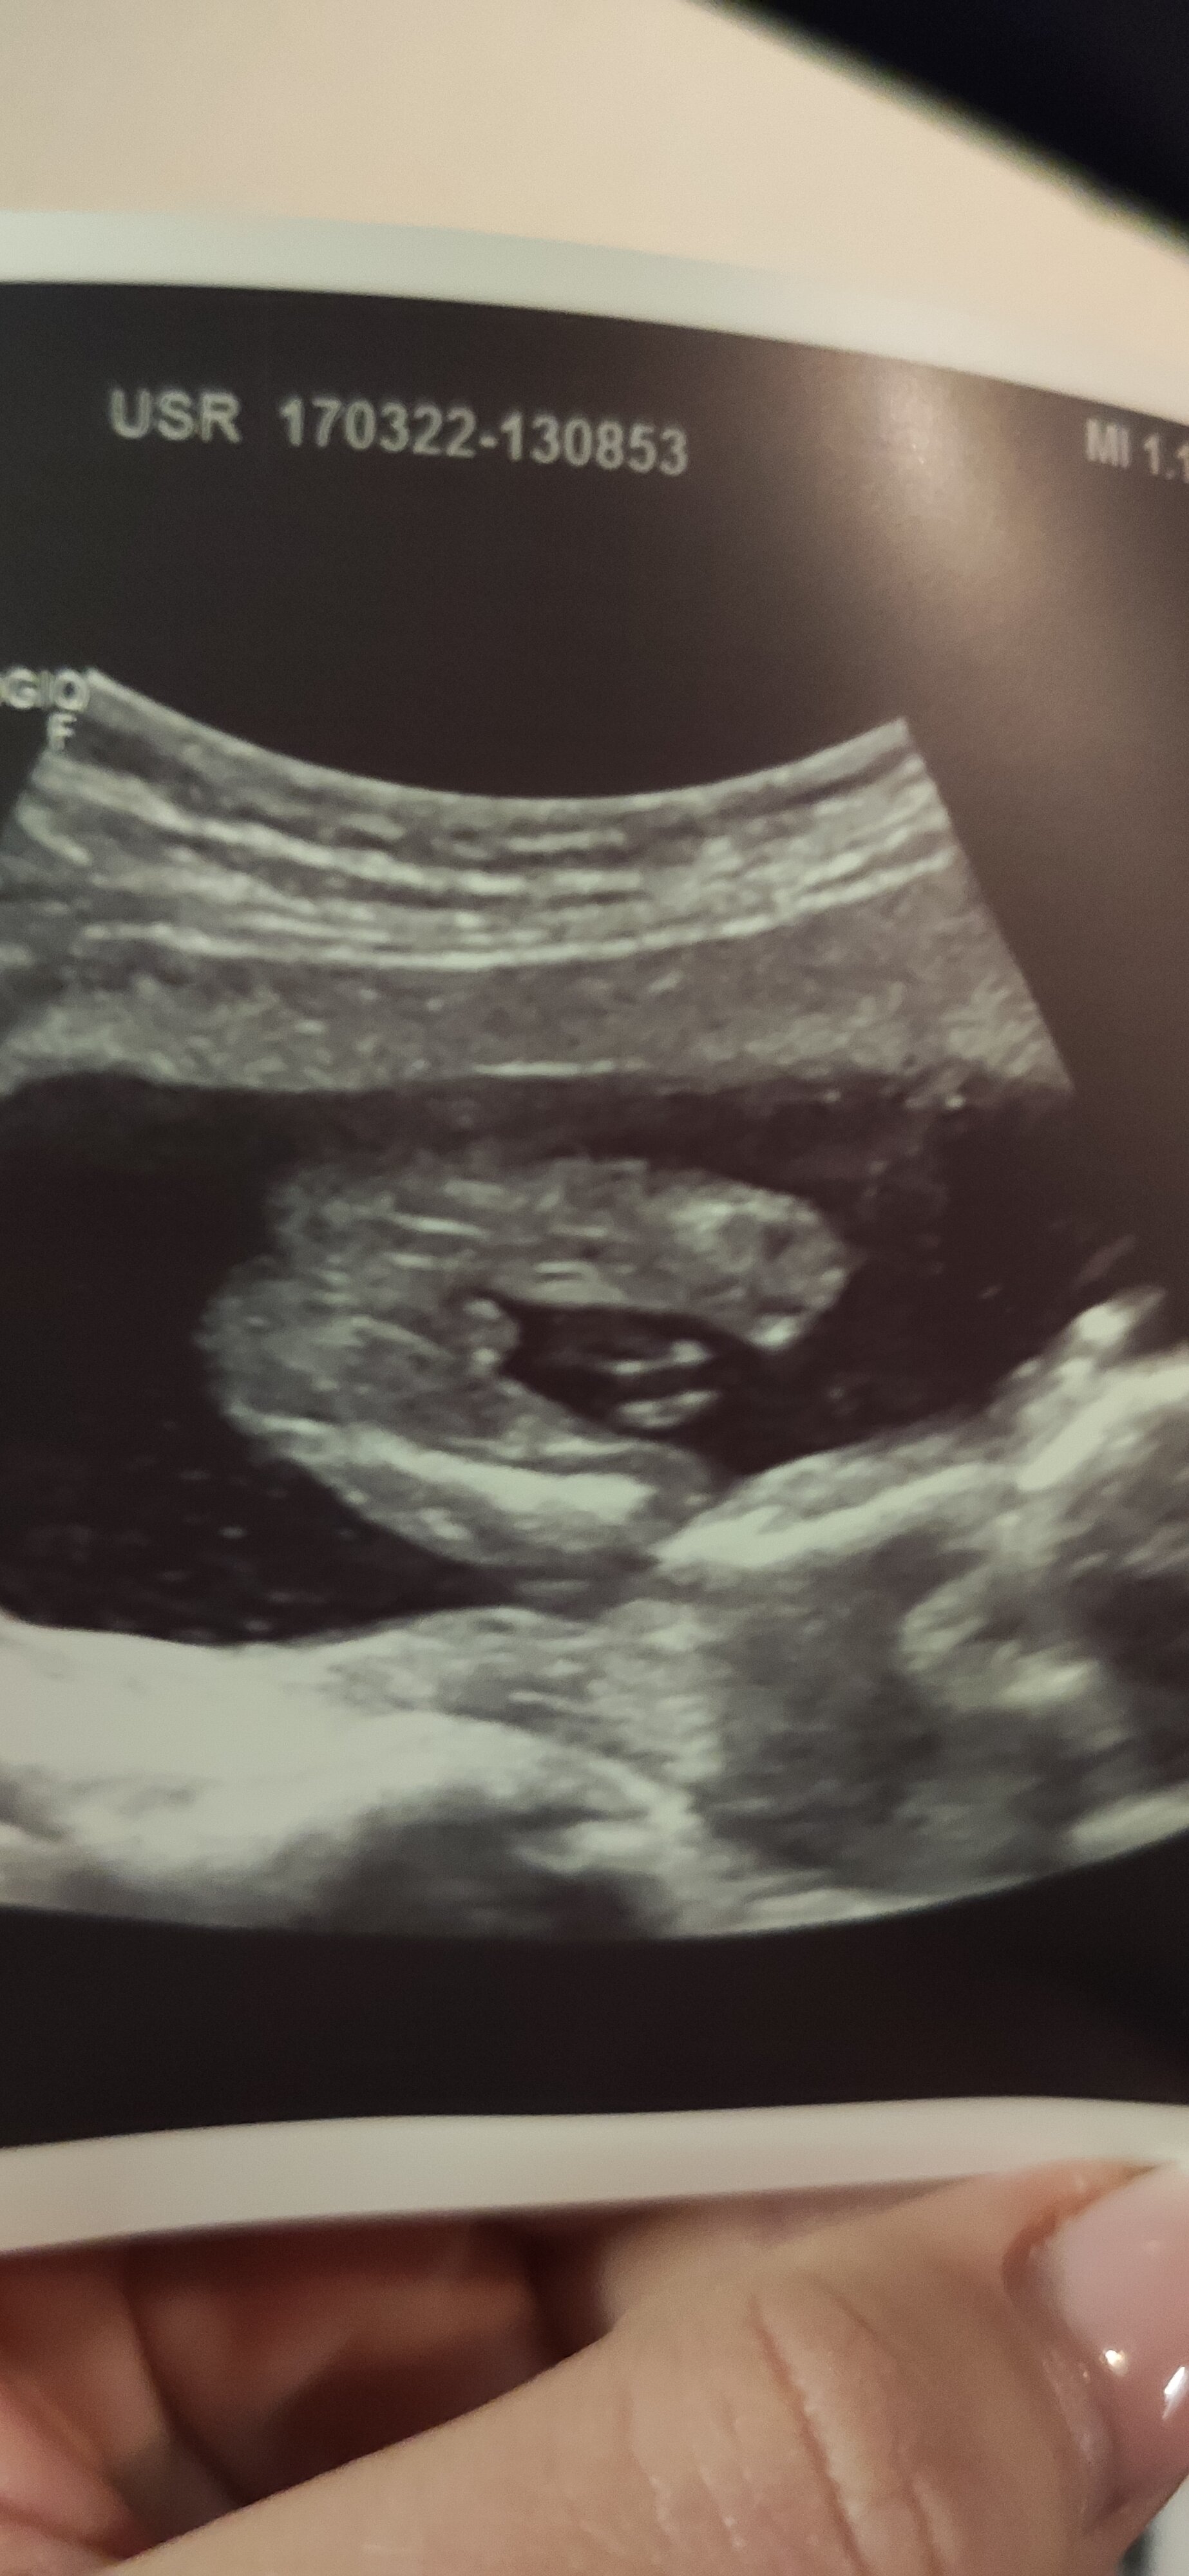

Hej ! Wracam z USG z 17w3d już więcej coś widać ale to jest jest dokładnie ta słynna 3 nogaU chłopca to w zasadzie trzecią nogę widać - tak dość nieproporcjonalnie to wygląda

Załączniki